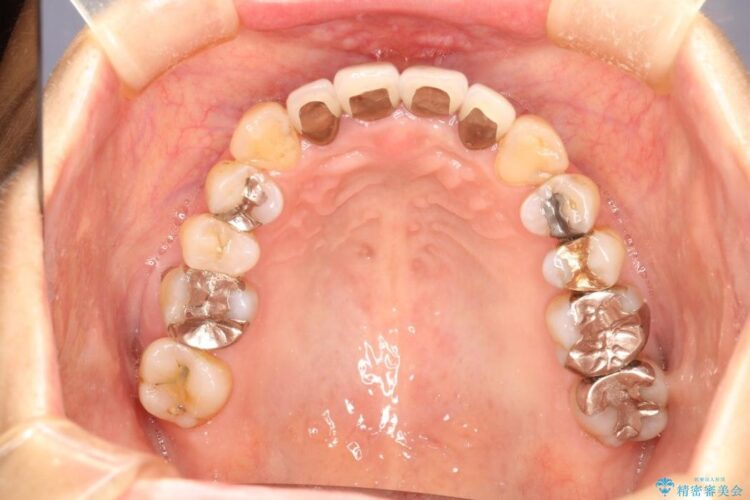

【50代女性】八重歯のインビザライン矯正 治療例

八重歯の改善を希望され来院されました。

当初はセラミックでの治療を希望されていましたが、噛み合わせと歯並びを治していく為に矯正治療を提案させていただき、インビザラインでの矯正を行う計画にしました。